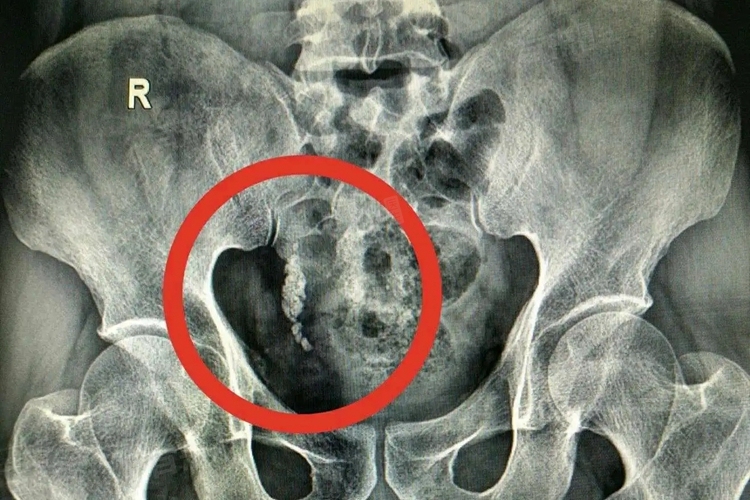

从医学角度来看,输尿管下段结石有8mm时自行排出体外存在一定难度,一般情况下难以实现。

- 输尿管本身存在生理性狭窄,这是结石排出的一大阻碍。输尿管有三个生理性狭窄部位,分别是肾盂输尿管连接处、输尿管跨过髂血管处以及输尿管膀胱壁段。8mm的结石相对较大,在通过这些狭窄部位时,很容易发生嵌顿,一旦嵌顿,结石就无法继续下行排出体外,还会引起输尿管痉挛,导致剧烈疼痛。

此外,结石在输尿管内停留的时间也是关键因素。如果结石长时间停留在输尿管下段,会引起局部黏膜水肿、增生,甚至形成息肉包裹结石。一旦出现这种情况,结石就被牢牢固定,几乎不可能自行排出体外,往往需要借助手术等干预手段才能取出结石。